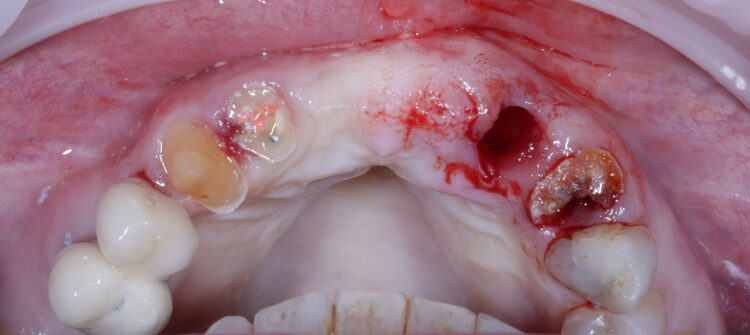

The UR2 was assessed and deemed unrestorable. The UR2, UL2 and 3 were then extracted as minimally traumatically as possible.

A miniflap was raised in the upper central region for this case to enhance visualisation for implant placement and augmentation. The guide was placed in the mouth and the standard guided surgery drilling protocols were followed. The new surgical kit improves workflow and intraoperative efficiency with the removal of spoons and a guide adaptor allowing for both guided and freehand use. During this step of the procedure, the guide was temporarily removed to double check the drilling angulation and verify this lined up with the pre-fabricated temporary bridge.

The two 3.3mm diameter Tapered Pro Conical implants were then placed through the guide at the pre-determined positions, angles and depths. Both implants achieved an insertion torque above 30Ncm.

Bone grafting was then performed, placing MinerOss X (BioHorizons Camlog) into the extraction sockets and the jump gap around the implant in the UL3 socket, to preserve the existing bone of the socket. This would help to minimise changes in the bone post-surgery and help to maintain the buccal profile of the ridge. The biomaterial is a bovine bone mineral matrix that has been proven to increase vertical bone height alongside implant placement.[vi] It has worked very well in my cases to date, offering a high turnover to bone for maximum stability and efficient results with immediate implant protocols.

A soft tissue graft was then performed, harvesting connective tissue from the palate and placing it in the sulcus of the UL3.

Non-engaging cylinders were placed onto the implants to connect to the pre-fabricated temporary bridge. A premade temporary bridge was connected, contoured and polished, with particular attention paid to the contour of the restoration and suturing with the aim of prosthetically guided soft tissue healing.